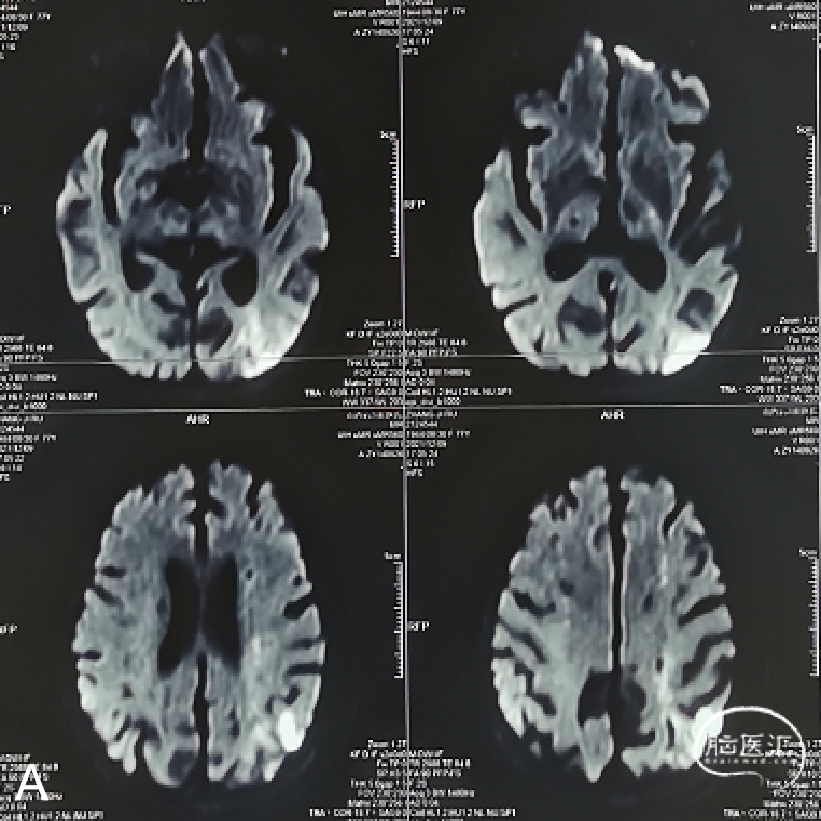

外院行头颅核磁示:左侧额顶枕叶急性脑梗死;颅内多发陈旧性脑梗死。

外院行脑血管造影示:左侧颈内动脉眼动脉段重度狭窄。